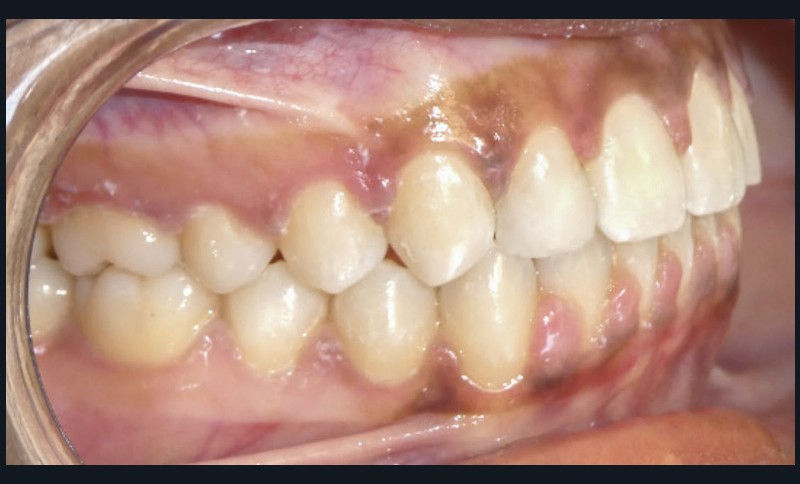

Les objectifs de traitement ont été atteints.

L’esthétique du sourire a été améliorée avec l’augmentation de la visibilité des dents maxillaires, ainsi que la restauration des incisives latérales au composite.

Le profil est plus harmonieux grâce à une diminution de la prochéilie mandibulaire par redressement de l’incisive mandibulaire (fig. 16- 18).

L’auto-transplantation de la 23 sur l’arcade, qui était en position très défavorable, et malgré un apex fermé présente de bons résultats. La radiographie rétro-alvéolaire (fig. 19) montre une intégrité de l’état radiculaire de la dent auto-transplantée. Un suivi régulier reste cependant nécessaire.